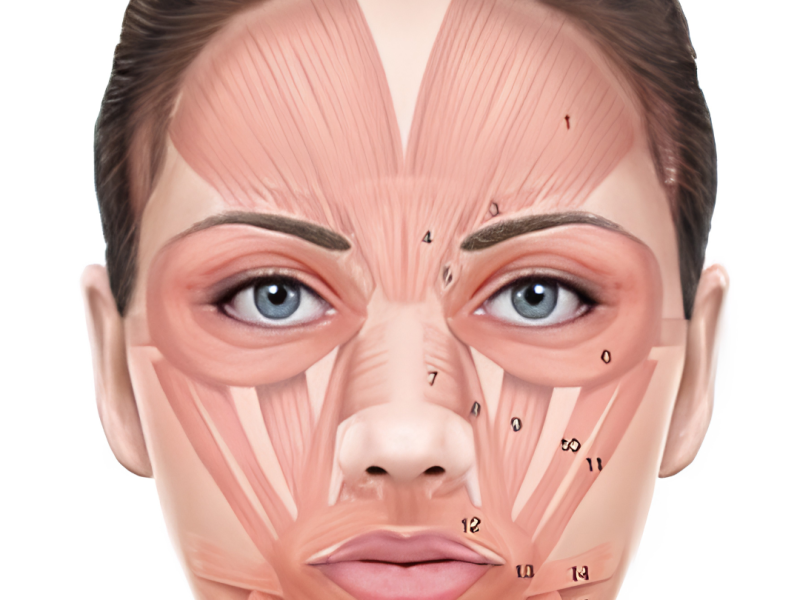

Conheça a anatomia facial para aplicar técnicas estéticas com precisão e segurança.